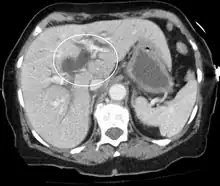

Posthepatic jaundice (obstructive jaundice) is caused by a blockage of bile ducts that transport bile containing conjugated bilirubin out of the liver for excretion.[30] This is a list of conditions that can cause posthepatic jaundice:

- Pancreatic cancer of the pancreatic head

Imaging

Medical imaging such as ultrasound, CT scan, and HIDA scan are useful for detecting bile-duct blockage.[41]